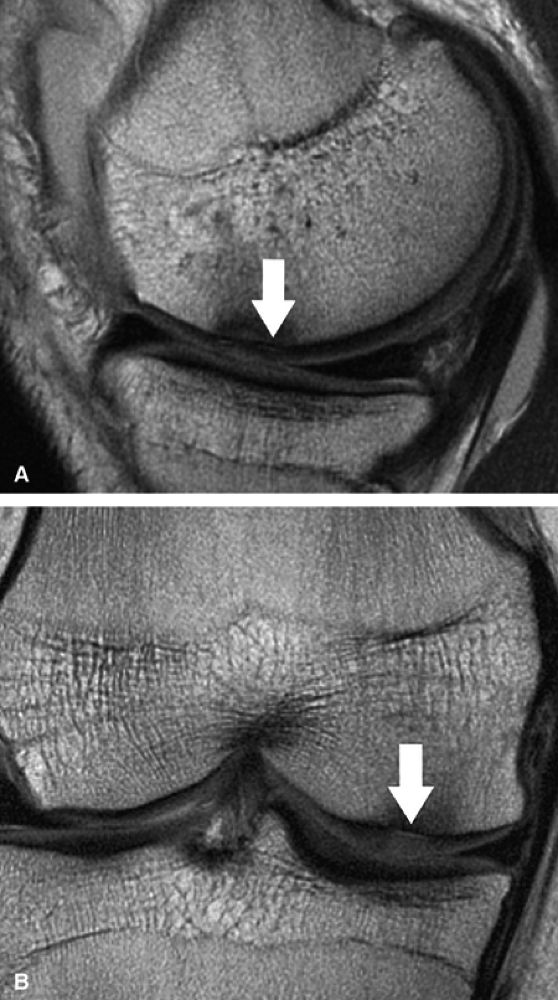

FIGURE 7.10 ● Sagittal (A) and coronal (B) fast spin-echo MR images of the knee in a 24-year-old professional football player. There is hyperintensity in the radial zone, indicating deep surface delamination (arrow), adjacent to the tidemark with no flap formation. There is also associated sclerosis of the subchondral plate. The patient underwent microfracture with a good clinical outcome.